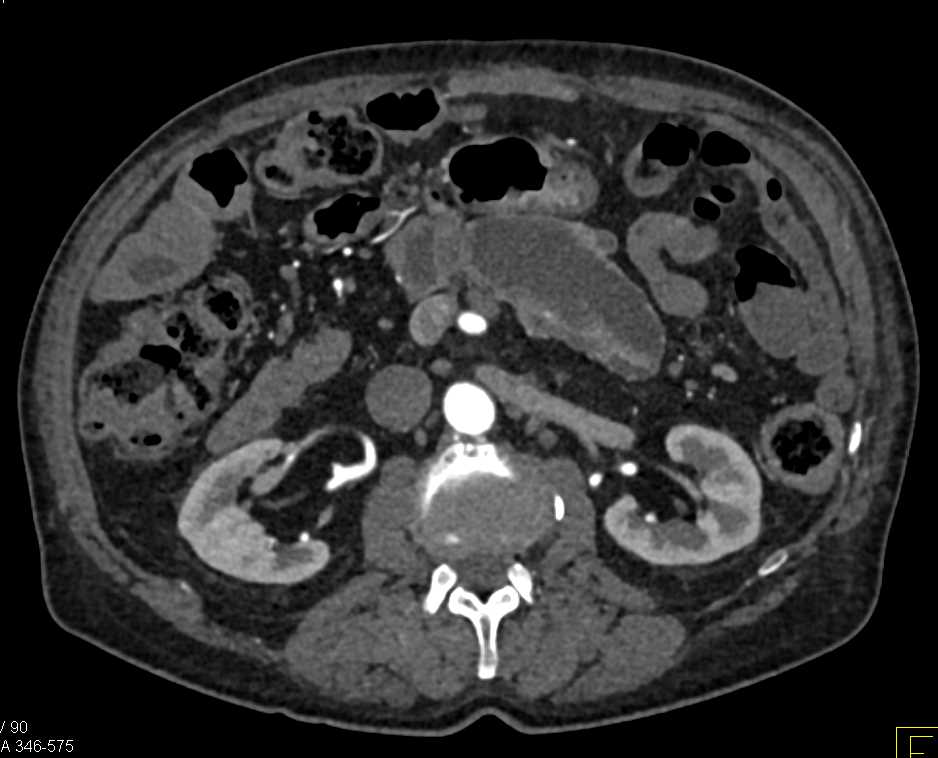

Serous Cystadenoma Head of Pancreas